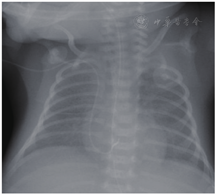

急查胸部X线片示PICC管端位于右心室内,导管远端弯曲(图1),急查心脏超声提示心室周围可见液性暗区包围,右室前壁心包腔内约5 mm(图2),左室后壁心包腔内液性暗区深约9 mm(图2),心包积液诊断明确,心包积液结果示:颜色乳白,透明度混,李瓦它试验阳性,细胞总数1 058×106/L,白细胞总数58×106/L,分类淋巴细胞0.13,分类中性粒细胞0.16,乳糜试验阳性,细菌培养阴性。血气分析提示:pH 7.03,PCO2 44 mmHg (1 mmHg=0.133 kPa),PO2 55 mmHg,BE-18.8 mmol/L, HCO3- 11.3 mmol/L,提示严重代谢性酸中毒。

患儿于PICC置管后3 d突然出现严重心动过缓及低血氧饱和度,听诊心音遥远,常规气管插管、心脏按压等抢救措施无效,行心脏超声提示:大量心包积液,胸部X线片提示PICC管端移位右心内,管端卷曲。行心包穿刺术抽出8 ml乳白色液体,积液化验提示为乳糜性质,故心包积液、心脏填塞诊断明确,考虑为PICC相关性。